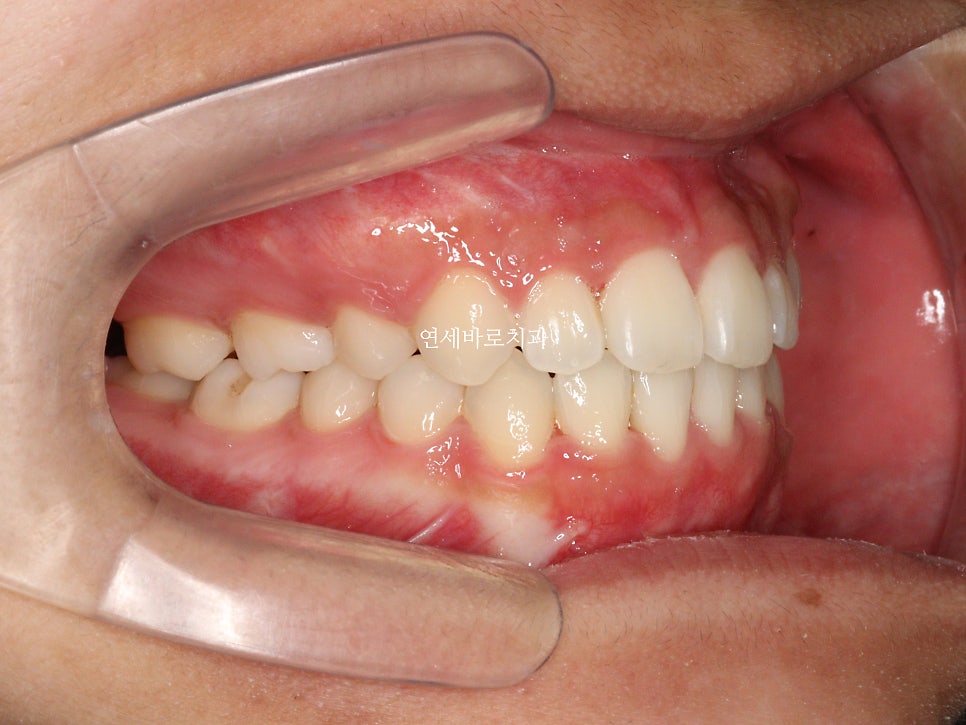

최근에 오셨을때 모습입니다.

아쉽게도 처음 끝날때와는 약간은 다른 중심선을 관찰하였습니다.

하지만 좌우 교합은 긴밀하게 유지되고 있었고 안모의 변화 등 다른 부작용은 관찰되지 않았습니다.